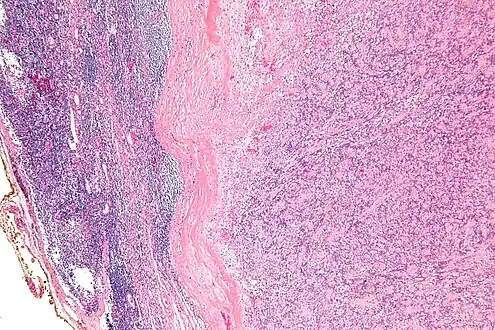

IPMs are diagnosed by examination of the tissue by a pathologist. They have a rim of peripheral lymphoid tissue (remnant of a lymph node) and consist of spindle cells with nuclear palisading. Red blood cell extravasation is common and blood vessels surrounded by collagen with (fine) peripheral spokes (amianthoid fibers) are usually seen.[3]

Intranodal palisaded myofibroblastoma with a thin rim of residual lymph node -

Low mag.Intranodal palisaded myofibroblastoma -